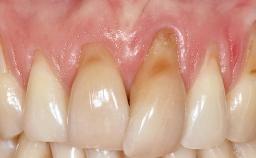

Periodontal Plastic Surgery and Prosthetic Procedures to Treat Peri-Implant Soft-Tissue Dehiscences

A 30-year-old woman was referred by her general dentist for evaluation of an esthetic complication related to previous implant treatment for congenitally missing maxillary lateral incisors. The patient’s chief complaint was the inadequate esthetic appearance of her smile. The case demonstrates the use of a combined approach to achieve optimal results. Two different flap designs - a tunnel technique and a coronally advanced flap - are employed based on the surgical objectives for the affected site.

Soft Tissue Contour and Volume Slightly compromised